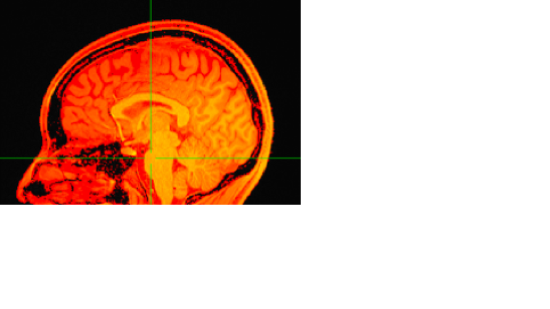

The display will now look something like this: